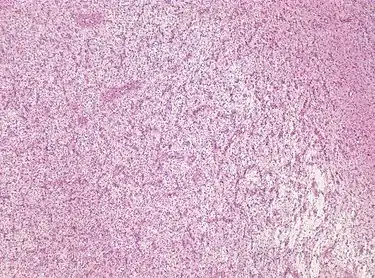

Photomicrograph displaying the AG tumor cells by histological evaluation, H&E stain. The striking characteristic of AG is that cells tend to cluster around brain blood vessels.[1]

For further confirmation, the clinicians require biopsy and immunohistochemical staining of the resected tumor after surgery. The infiltrative AG cells display positive results for several immunostainings, especially the glial fibrillary acidic protein (GFAP) and epithelial membrane antigen (EMA).[1] Clinicians also observe a specific dot-like pattern from the stained EMA photomicrograph.[3] Other specific AG immunohistochemical tests include Ki-67 proliferative marker, neurospecific nucleoprotein (NeuN), protein 53, synaptophysin (Syn), oligodendrocyte transcription factor-2 (Olig-2) and creatine kinase (CK).[3] In the 2016 WHO classification of CNS tumors, AG is characterised as GFAP-positive, NeuN-positive and low Ki-67 proliferative rate with a perivascular growth pattern.[13]

Photomicrograph displaying the AG tumor cells by histological evaluation, H&E stain.Characteristics of AG: low Ki-67 proliferative rate, GFAP-positive, NeuN-positive, S-100-positive, Protein53-negative, Syn-negative, Olig-2-negative, CK-negative.[3]